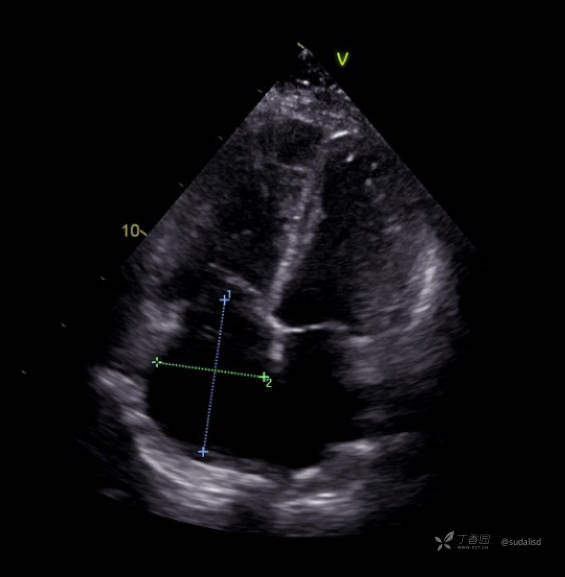

心脏彩超四腔心切面如下图。